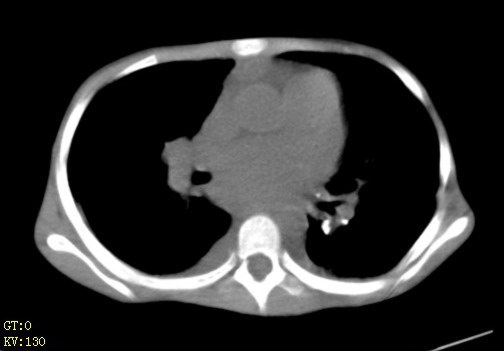

女,12岁,气促、咳嗽2天,3个月前查胸片示:两肺感染,急诊入院查ct,血常规等未检查。

先心(室缺?)、左室大,心功能不全;肺部感染

心衰 肺水肿

左肺上叶改变考虑继发性肺结核,余双肺重症肺炎不排除h1n1。双侧胸腔少量积液。

两肺感染,双侧少量胸腔积液;肺淤血及心脏改变,考虑心功能不全改变。学习了,望能反馈随访结果。

1、左心房、左心室增大,考虑左心衰, 2、肺水肿合并感染 3、双侧胸腔积液

双肺中下野不规则片絮状阴影,中外带明显,双侧胸腔少量积液,心影增大,心腔密度减低,隆突下及左侧气管旁见钙化淋巴结影,考虑双肺感染、心衰;建议结合临床除外h1n1并急性心衰,先心不能排除。

两肺多发片絮状模糊影,以下肺外带居多,内见支气管气像,纵膈窗未减影,两侧胸腔积液,心影增大,结合心超,支持重症肺炎,非常时期,甲型h1n1流感不排除。